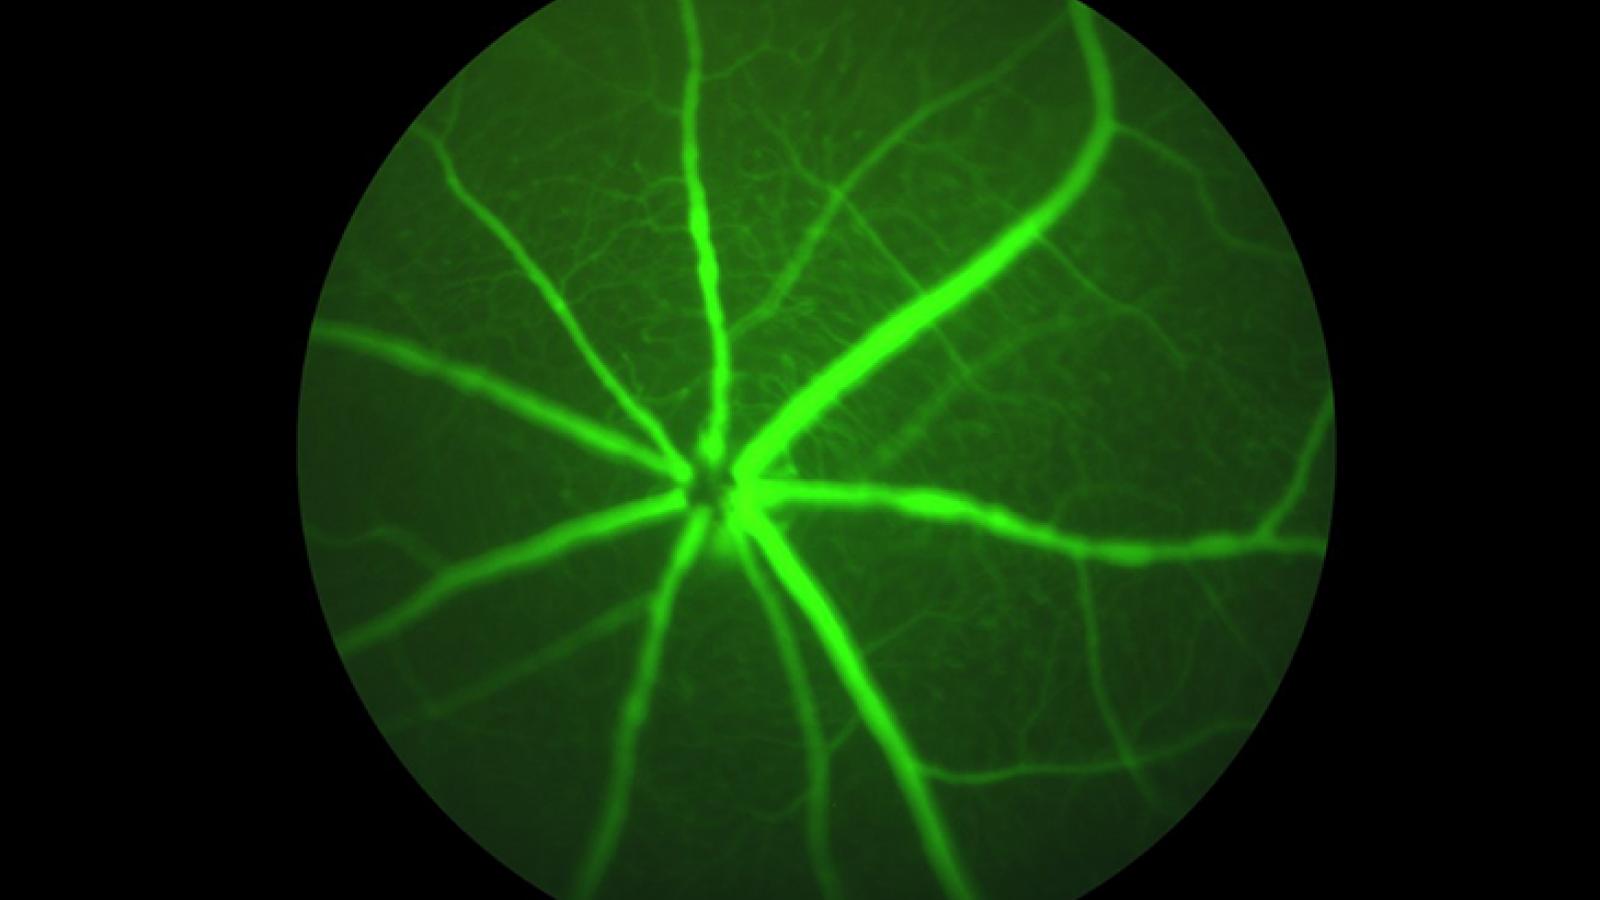

Pre-clinical research studies investigate a wide range of diseases, including infectious disease, cancer, immunology, cardiovascular disease, metabolic disorders, kidney disease, liver disease, digestive disorders, neuromuscular disease, sleep apnea and eye disorders. The controlled environment of the vivarium allows the therapeutic effects of exercise, nutrition, and novel therapeutics to be examined in unique rodent models. The vivarium is managed by the Animal Care Quality Assurance office in conjunction with the School of Medicine Scientific Directors for the Vivarium.